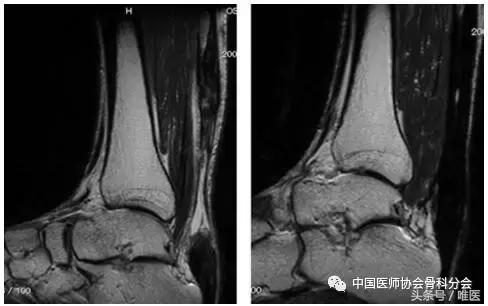

在术前T2加权图像中,在22例患者中观察到肌腱状肌腱增厚和腱内弥漫性高信号改变,但这些患者术后6个月MRI在MRI腱上有均匀的低信号改变(图3)。在其余8名患者中观察到肌腱变薄。在这8例患者中的6例中,术前观察到弥漫性腱内高信号变化。但术后6个月在MRI中可见肌腱形腱增厚和均质的低信号改变(图4)。

图4:一个63岁男性肌腱的T2加权MR图像。左:术前图像显示损伤后3个月的腱变薄和弥漫性腱内高信号改变。右:术后6个月时显示梭形肌腱增厚和均匀的低信号改变。